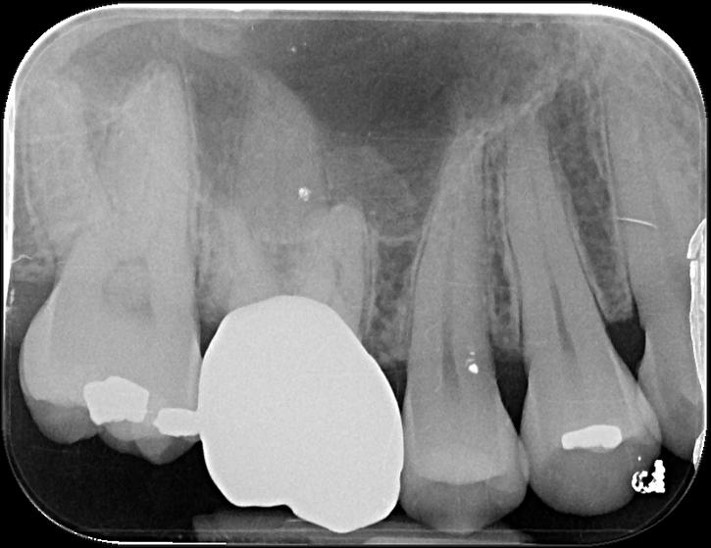

通常患者的蛀牙都在鄰接面、牙齦下,因此傳統必須進行根管治療等治療,但如果沒有蛀至牙髓,早期將牙齦下蛀牙以水雷射切除蛀牙與牙髓,戴上臨時假牙觀察一個月,如果沒有牙髓相關症狀,接著再印模製作假牙,而現今全鋯冠硬度與美觀都相當理想,為現今治療的最前線治療。

水雷射牙齦切除手術

全鋯冠

治療後,咬合良好

治療後,密合度良好

術前、術後比較

幾年下來,這一類連續的治療,長期的癒後相當穩定,因此對於有心保留牙齒的患者,提供了另一個方法,是植牙之外的另一個重要的治療方式。